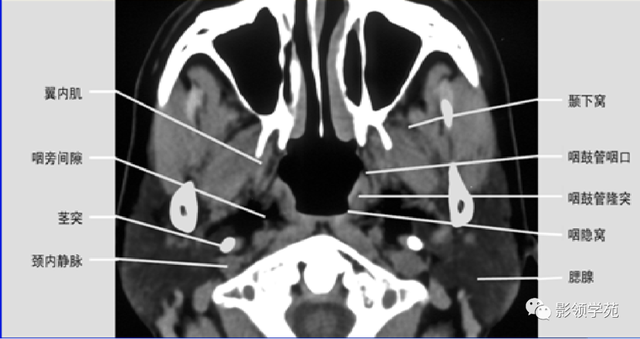

腮腺位于下颌后窝品味 肌后部,上抵颧弓,下达颌骨下缘,形态类似三角形,长6cm,宽3~4cm,最厚处约1.0cm。腮腺导管始于腺泡腔,经润管→纹管(小叶内) →渗透 管,总导管启齿 于口腔内,全长3~6cm,外径2~4mm。血供为颈外A分出的颞浅A和颌内A分支。静脉最后汇入面总、面后和颈外V,穿行腮腺内的有面N、颈外A。

腮腺内外肿块的定位:

腮腺肿瘤外缘与腮腺之间有无脂肪层存在;

肿瘤较大时凭证 茎突推压的偏向及肿瘤最大径;

腮腺深叶肿瘤与咽旁间隙肿瘤判别 :

腮腺深叶肿瘤多呈哑铃状,病变常致茎突和下颌支之间的距离增宽,咽旁间隙脂肪带常内移;二腹肌后腹后移。

咽旁前间隙的肿瘤常致咽旁脂肪带外移,在肿瘤和腮腺深叶间有脂肪距离 ,病变致其茎突下颌沟增宽少见。

咽旁后间隙肿瘤致二腹肌后腹前移。